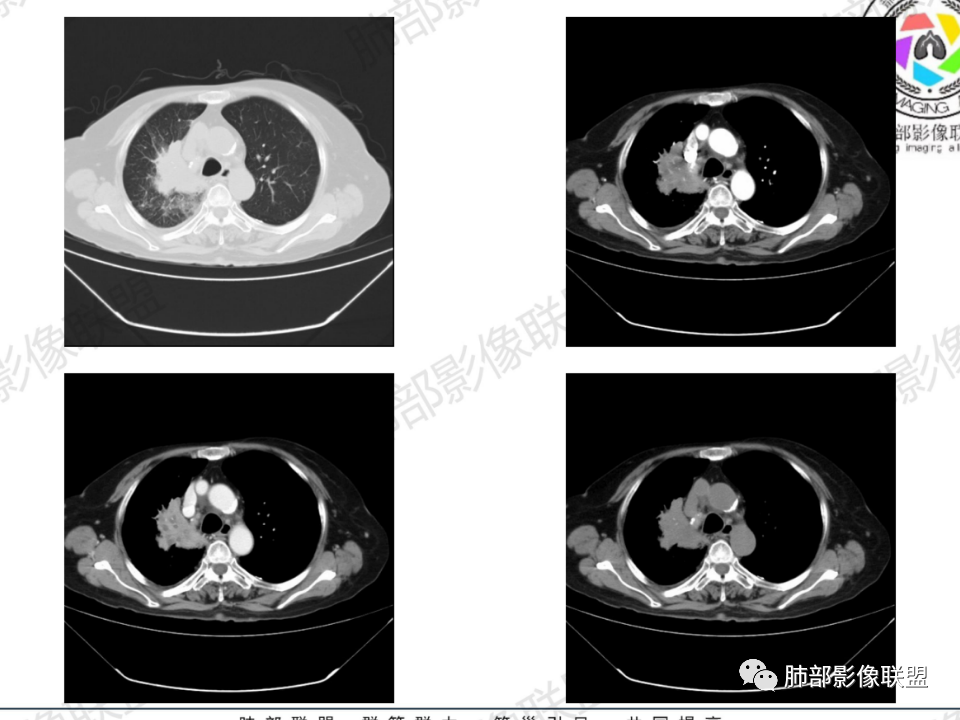

老年患者,病程中等,有咳嗽/喘息/低热症状,肿瘤标志物升高,感染标志物不高,右上肺新生物,中央型,边界清楚,有分叶,支气管截断,内有坏死,不均匀强化,考虑肺癌,鳞癌?

那个人:老年女性,亚急性病程,咳嗽发热。有垂体前叶功能减退,目前激素替代治疗,长期激素,量小,不知道累积量,没有目前激素水平指标。既往有淋巴结结核病史。肿瘤标记物Ca125升高。血沉升高,C反应蛋白轻度异常。影像,右肺上叶靠近肺门团块影,右肺门淋巴结钙化肿大,支气管狭窄,局部增厚,团块影外朝内改变,强化明显,血管破坏不明显,有粘液。和纵隔胸膜分界清楚,周围肺组织有斑片渗出影,右侧胸腔积液,考虑炎性?结核?支气管镜检查除外恶性飞鹰行动:老年患者,影像表现 右肺上叶占位性病变,边界清楚,有分叶征,内见细小钙化,右肺上叶支气管截断,增强病灶不均匀强化,病灶内有条状坏死区(扩张的支气管?),纵膈内未见增大淋巴结,考虑炎性病变,结核可能。一切∮随缘:右肺上叶实性肿块形态不规则,呈三角形,边缘分叶,边界伴有磨玻璃影,近段支气管未见明显显示,可能堵塞,病变平扫密度均匀,增强后可见低密度坏死无强化,周围略强化,右肺下叶散在结节。心包积液,及右侧胸腔积液,临床:有低热,低蛋白血症,肿瘤标记物高,考虑恶性:腺癌,神经内分泌癌(强化偏弱了),淋巴瘤,鉴别:结核红星:老年女性患者右肺上叶,肺门上区 分叶状肿块 ,右肺上叶支气管显示不清,增强扫描肿块,中等程度强化可见小斑片状坏死区,病灶内部可见斑点状钙化灶,病灶周围可见斑片状及小斑点状影,纵膈淋巴结增大,其他区域,胸膜下可见斑点状钙化。考虑肉芽肿性病变,结核的可能性大。老年患者最排除肿瘤性病变腺癌。土娃:右上肺不规则肿块影,边缘分叶,边界磨玻璃影欠清,病灶分叉状,内见点状钙化影及坏死灶,支气管堵塞,病灶增强强化不明显。考虑瘤样结核,鉴别淋巴瘤。张小兵:老年女性,亚急性病程,右肺上叶见不规则肿块,边缘平直凹陷为主,周围GGO边界不清,内见点状钙化及坏死灶,增强持续性渐进强化,右侧少量胸腔积液,双肺门及纵隔肿大淋巴结伴钙化,综合考虑慢性炎症。saf:老年患者,影像表现 右肺上叶占位性病变,边界清楚,有分叶征,增强病灶明显不均匀强化,纵膈内未见增大淋巴结,考虑炎性病变,结核可能。小兜:老年女性,咳嗽喘息一月,发热三天,肿瘤标志物升高,长期激素替代治疗。CT示右肺上叶近肺门不规则实变影,周围伴磨玻璃影,增强持续性渐进强化,内部血管破坏不厉害,内部可见多发条形低密度灶,右侧胸腔可见少量积液,双肺门及纵隔可见钙化淋巴结,考虑为炎性病变,结核可能玫:女,79咳嗽,喘息一月,发热三天入院,右肺上叶不规则形软组织密度肿块影,边界清晰,边缘见分叶及细短毛刺,病灶内见点状钙化影及稍低密度区,病灶边缘呈磨玻璃样改变,增强扫描,病灶呈不均匀性强化,考虑炎性病变,鉴别鳞癌。大雄:老年女性,既往诊断淋巴结结核,提示已治愈,近2年服用激素,诱导结核复燃→发热;纵隔肺门淋巴结肿大钙化,压迫支气管,右肺上中下叶支气管均狭窄→喘息咳嗽;尖段支气管受累闭塞→肺不张、支气管粘液栓;累及胸膜,结核性胸膜炎并胸水→右侧胸痛;实验室,血沉快,CA125高,低蛋白,符合;下一步,支气管镜尖段支气管刷检抗酸染色周太狼:老年女性,亚急性病程,肿瘤标志物升高。CT示右肺上叶尖段不规则肿块影,有分叶、收缩,周围伴磨玻璃影,增强渐进强化,内部可见多发条形低密度灶,右侧胸腔及心包少量积液,纵隔内淋巴结稍增大。倾向于恶性病变,肺癌伴阻塞性炎变可能。丽:老年女性,右肺上叶不规则软组织肿块,边缘清晰,内密度不均,可见点状钙化及粘液栓,周围可见片状高密度影,增强后均匀强化,内多发低密度,纵膈多发钙化淋巴结,考虑结核可能大,建议结合支气管镜检查除外肿瘤宇宙:右胸廓缩小,右肺上叶团块影及不张,平直边,周围磨玻璃影,纤细胸膜牵拉,上叶尖段支气管堵塞,明显延迟强化,可见支气管粘液栓,两肺门钙化淋巴结,右侧胸水,考性炎性肉芽肿,鉴别腺癌王秀仙:右肺上叶肺门区肿块,上叶支气管开口阻塞,形态不规则,密度不均,内可见支气管粘液栓及多发小灶性坏死,周围磨玻璃影边缘模糊,渐进强化,右侧胸腔积液、胸膜钙化,考虑炎性肉芽肿性病变,慢性炎症。鉴别鳞癌,结核。刘丹:老年女性,右肺上叶肿块伴钙化,右肺上叶支气管截断,增强后均匀强化,周边可见点片状模糊影,右侧胸腔积液,右肺门淋巴结增大,考虑占位并阻塞性炎症,肿瘤?结核?建议纤支镜检查。小飞:右肺上叶纵隔旁软组织肿块,边缘深分叶、长毛刺及毛刷样短毛刺,边缘磨玻璃影,磨玻璃边界模糊,支气管截断,平扫密度不均,可见点状钙化,增强不均匀明显强化,心影增大,心包积液,右侧胸腔积液,考虑恶性肿瘤,腺癌?秦化君:右肺上叶不规则分叶软组织密度肿块,边缘清晰,胸膜牵拉,周围花花草草,上叶尖段支气管阻塞,内可见点状钙化,增强后密度不均可见支气管粘液栓及坏死区,内见血管分枝。中间段及中叶,下叶支气管狭窄,壁见钙化。右肺门淋巴结肿大,右侧胸腔积液,心包粘连肥厚。考虑1右上肺恶性病变,鳞癌?2右肺多叶段支气管狭窄,考虑支气管内膜结核?3胸腔积液及肺门淋巴结肿大,转移?风儿:老年女性,右肺上叶肿块,形态不规则,外围大内带小,边缘分叶膨隆平直及毛糙,密度不均,内见支气管粘液栓及多发小灶性坏死,坏死边缘清晰 ,渐进强化,上叶尖段支气管阻塞,叶支气管壁有局限性增厚,邻近胸膜腔微积液;纵隔及双肺门淋巴结肿大,部分钙化,右侧胸腔积液、心包积液、胸膜钙化,考虑炎性,肉芽肿性结核可能性大。鉴别鳞癌,女性及血供均不支持;腺癌,坏死边界太清晰。流心明智:老年女性,79岁,咳嗽、气短1月,发热3天。胸CT:右肺上叶见不规则肿块,边缘有膨隆、有平直凹陷,周围GGO边界不清,病灶内见点状钙化、粘液栓,尖段支气管未见,增强持续性渐进强化,右侧少量胸腔积液,双肺门及纵隔肿大淋巴结伴钙化,肺动脉增粗。考虑:右上叶尖段堵塞并慢性炎症,支气管TB并结石?鉴别Ca

右肺体积小,提示既往结核

支气管影

前,后段都在,没有堵塞

支气管壁增厚,周围磨玻璃边界不清,提示炎症。胸膜下钙化符合结核

近期发热符合感染

这个层面往上应该是尖段,显示不清

背段支气管周围增厚伴钙化,符合结核改变

胸腔积液并胸膜钙化,符合结核;

结核是肯定有。现在最大问题是尖段

近端显示不清,但是远端是粘液栓,可以认为是还行的

如果是近端鳞癌,远端应该会堵塞,不会整个肿块里面还有较为通畅的支气管

这个区域我们看到密度与周围一致,并不是肺癌伴周围不张的感觉,所以鳞癌暂时是不支持的

临床信息:老年女性,亚急性病程,咳嗽发热。有激素使用史。既往有淋巴结结核病史。肿瘤标记物Ca125升高。血沉升高,C反应蛋白轻度异常。 影像所见:右侧胸廓相对狭小,右肺上叶不规则团块影贴附纵隔旁,轻度分叶,整体密度较均匀,偶见钙点。

相应上叶尖端及前段支气管开口未能追踪(阻塞),开口处见钙化。病灶渐进性强化,并衬托出较完整尖段及前段含液支气管影。支气管开口区域未见异常高密度强化(如类癌等)及相对乏血供区(如鳞癌)。病灶区未见液化坏死。右上纵隔及胸廓入口区未见病灶胸膜外突破(栽赃)。

右肺上叶后段等区域散在片状影,边界不清(提示渗出性病灶)。

纵隔及双肺门见钙化淋巴结。心包积液,右侧胸腔积液(提示存在活动新病灶)。双侧胸膜下见多发斑点状钙化,胸廓变形(提示存在结核基础病变可能)。 诊断意见:综上,右肺上叶块状影更符合继发性肺结核。 最后小结:既往诊断淋巴结结核,提示已治愈。近2年服用激素,可疑诱导结核复燃,也可引起发热。纵隔肺门淋巴结肿大钙化,压迫支气管,右肺上中下叶支气管均狭窄,所以引起喘息咳嗽。尖段支气管受累闭塞,导致肺不张、支气管粘液栓,出现条状无强化区。病变累及胸膜,导致结核性胸膜炎并胸水,引起右侧胸痛。实验室检查血沉快,CA125高,低蛋白,均符合结核。下一步,建议支气管镜尖段支气管刷检并抗酸染色。(本段摘自於雄老师精彩发言)